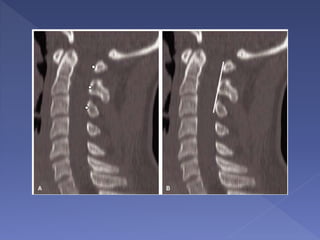

• Extensive

degenerative changes

noted but no gross

evidence of

malalignment

• The ALL, LF and

PLL are disrupted.

• There is widening

of the interspinous

distance

• Edema in the

posterior paraspinal

soft tissues

• damaged

intervertebral disc